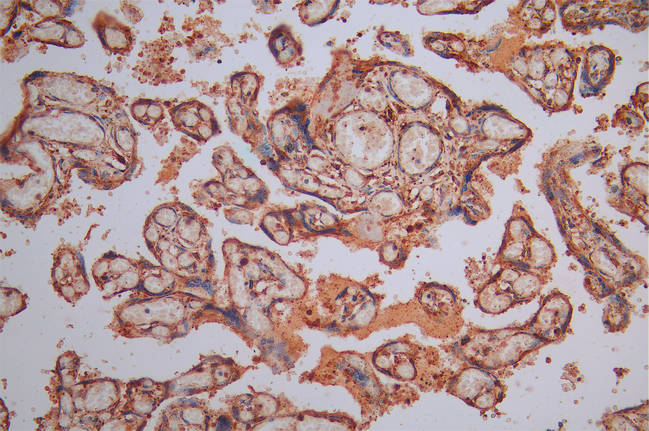

IHC image of CSB-RA004458MA1HU diluted at 1:300 and staining in paraffin-embedded human placenta tissue performed on a Leica BondTM system. After dewaxing and hydration, antigen retrieval was mediated by high pressure in a citrate buffer (pH 6.0). Section was blocked with 10% normal goat serum 30min at RT. Then primary antibody (1% BSA) was incubated at 4°C overnight. The primary is detected by a Goat anti-Mouse IgG labeled by HRP and visualized using 0.05% DAB.